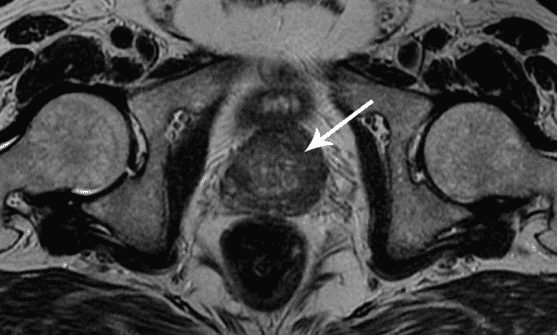

Prostatakrebs bei einem Mann mit 58 Jahren.